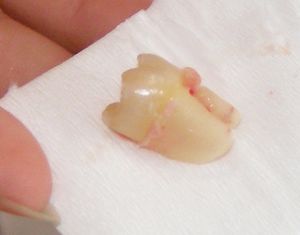

الخلع